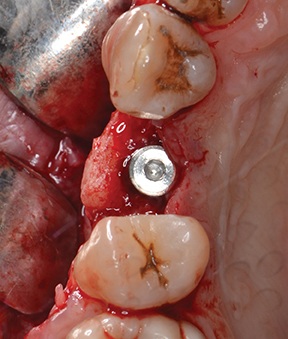

After removing fixation screws (Fig. 22), a 3.75 × 13 mm implant was placed with a final torque >35 N·cm (Figs. 23–24) and the flap was closed with 4-0 monofilament interrupted sutures (Fig. 25).

Block by Block

Fig. 23: 3.75 × 13 mm implant placed (buccal view)

Fig. 24: 3.75 × 13 mm implant placed (occlusal view)